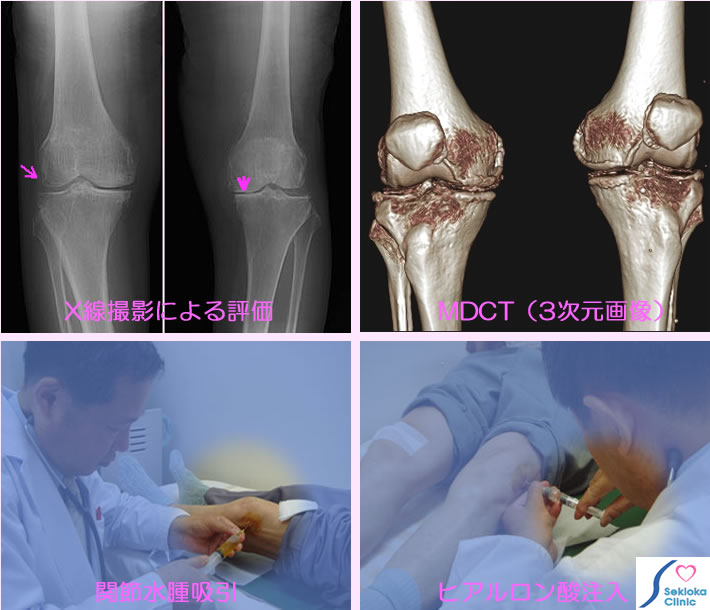

膝の視診と触診でもほぼ診断できますが、病気の程度・進行度の評価のためX線撮影を行います(上段左の画像)。関節軟骨の減少によって関節裂隙が狭くなる、軟骨部の石灰化、骨棘(余分なとがり)などを認めます。上段右はMDCT3次元画像で、石灰化、関節の狭小化などよくわかりますが 変形性関節症のみの疑い時は通常検査には使いません。

治療 関節に水が貯まっている時(触診でほぼわかる)は排出後、ヒアルロン酸を注入(下段右写真)します。この注射を週に1回、5週間ほど続けます。当院でヒアルロン酸注射は既に130名以上の方が受けておられるが約8割の方に痛みの消失、軽減が見られる。他に運動療法や痛み止めを併用することもあります。